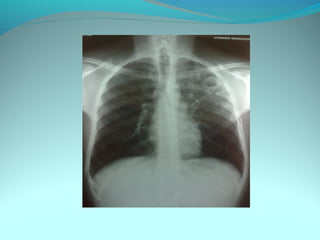

Opacité micronodulaire bilaterale diffuses et uniformement repartis

sur les 2 poumons realisant l’aspect d’une miliaire a petit grain

On note opacité latero trachiale ovalaire de 3cm de grand axe vertical

a limite ext des ADP médiastinale

Une opacité hilaire droite de 15 mm d’epaisseur

DIAGNOSTIC:

Miliaire tuberculeuse avec ADP mediastinal

Lymphome avec miliaire

Sarcoidose type2